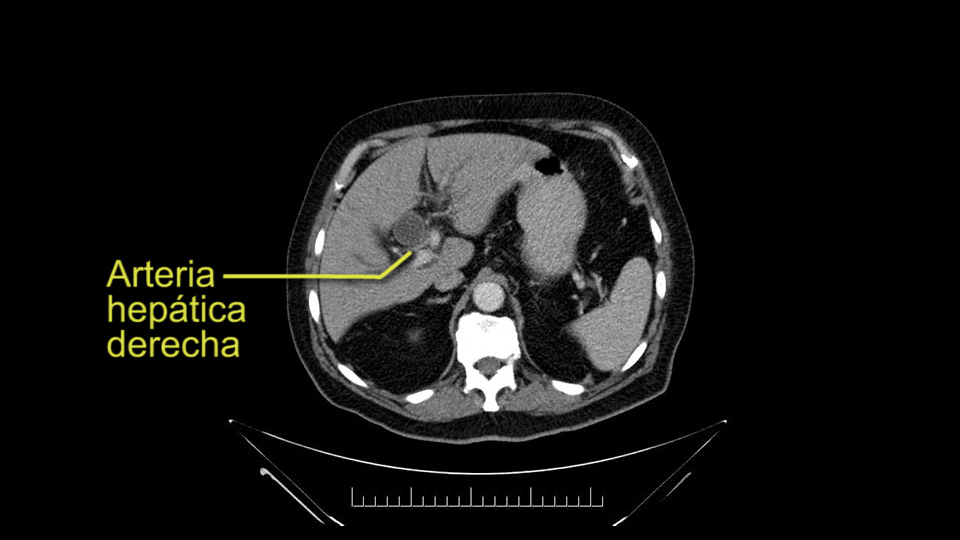

He has normal arterial anatomy: no accessory or replaced right hepatic artery, which is important because sometimes the right hepatic artery can come behind the neck of the pancreas and you have to be careful of that in a Whipple dissection.

Then you look for anomalies. The one you worry about the most doing a Whipple is a replaced or aberrant right hepatic artery coming off the SMA at its origin. So again, find the SMA. You can find it because the renal vein goes through it. Follow it up, up-up-up. Nothing coming off of there that I can see here. Nothing coming off of it, nothing coming off of it and just to confirm it, look at the celiac trfurcation. There’s the celiac, there’s the bifurcation, there's the splenic artery, hepatic artery. Make sure there’s a right, which there is here. The right usually goes under the bile duct: important when you’re going around the bile duct to do a Whipple. A replaced right goes under the portal vein and the bile duct way over here on the right. That’s about it.

To plan a pancreatoduodenectomy, we start by reviewing the vascular anatomy, especially the origin of the celiac trunk, here, in front of the aorta, looking for any evidence of stenosis. In addition, we look at the origin of the superior mesenteric artery, to look for any branches, and any replaced right hepatic arteries coming from the superior mesenteric artery; which does occur in about 12% of the population.

The second point about the vascular anatomy-, is to again look for right hepatic arteries in the hilum, coming from the superior mesenteric artery by palpating-through the Winslow Hiatus. Usually we will check for a pulse in the posterior aspect of the hepatic hilum, where a right hepatic artery should not usually be found. In this case, the precaution is to avoid an accidental ligation of the right hepatic artery that might jeopardize perfusion of the right lobe, or if there is a completely replaced hepatic artery that can put the liver circulation at risk.

Para planear una pancreatoduodenectomía, se debe revisar la anatomía vascular, especialmente el origen del tronco celíaco, aquí, por delante de la aorta, buscando areas de estenosis y por otro lado, el origen de la arteria mesentérica superior, para evaluar -sobre todo- si hay ramas, arterias hepáticas derechas provenientes de la mesentérica superior; lo cual ocurre en alrededor del 12% de la población.

E l segundo punto de la anatomía vascular, es nuevamente buscar arterias hepáticas derechas, en el hilio, provenientes de la mesentérica superior y eso lo hacemos palpando -a través del Hiato de Winslow- el hilio hepático y usualmente sentiremos un pulso en el aspecto posterior del hilio hepático, donde no debe ir el recorrido usual de la rama derecha de la arteria hepática. En este caso, la precaución es no realizar una ligadura accidental de la arteria hepática derecha y poner en riesgo -posiblemente- la perfusión del lóbulo derecho, o aún esta arteria puede reemplazar completamente la arteria hepática y poner en riesgo la circulación del hígado.

Confirm arterial anatomy: RHA, GDA

I am a believer in pylorus preservation. And in this case I see no reason why that wouldn't be possible. Mobilize the duodenum, divide the gastroepiploic vessels and divide the duodenum. I try to divide it with a linear stapler about four centimeters from the pylorus to have adequate length for my GI anastomosis. This facilitates exposure of the head neck of the pancreas. I find the gastroduodenal artery. This patient has normal arterial anatomy. Always on every preoperative CT scan I look to see if there is a replaced right hepatic. In this case I did not see one. Regardless of how confident I am I always look carefully for variant anatomy. I always do a clamp test on the GDA before ligation. I doubly ligate the GDA with not just a tie but a suture ligature because of the risk of GDA blowout in patients with a leak.